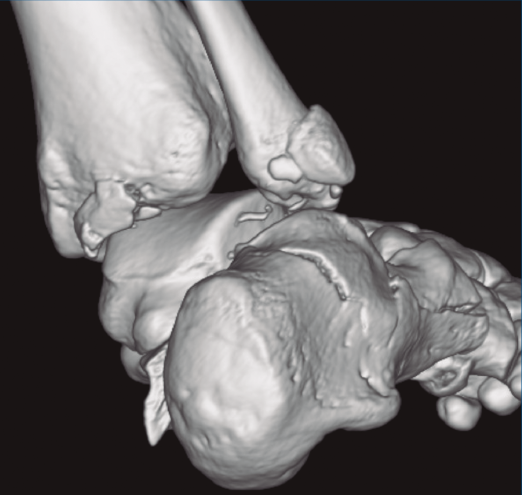

Figura 1. Luxación del astrágalo en mortaja tibioperonea, fractura maléolo peroneo y espacio subperoneo ocupado por calcáneo.

Figura 2. Fractura maléolo peroneo y tibial posterior. Trazo entre fragmento anteromedial y posterolateral.

Figura 3. Desplazamiento entre fragmento anteromedial (sustentaculum tali) y posterolateral (tuberosidad).

Se trata de un varón de 19 años que ingresa en reanimación tras precipitarse desde una altura de aproximadamente 10 metros. El paciente presenta una fractura estallido de L3 con afectación del canal medular junto con una fractura del vértice inferior de L4, así como una fractura luxación de calcáneo, asociada a una fractura del maléolo peroneo y del maléolo tibial posterior (Figuras 1 a 6) diagnosticadas mediante TC total body (por eso no se dispone de radiografías simples al momento del ingreso). Como podemos comprobar, se trata de una fractura de doble trazo de tipo hundimiento/depresión de la carilla articular (Figuras 5 y 6).

Figura 4. Luxación fragmento posterolateral.

Figura 5. Fractura maléolo peroneo, luxación astrágalo, fractura de doble trazo en calcáneo.

Figura 6. Fractura de doble trazo; se evidencia afectación de la articulación calcaneocuboidea.